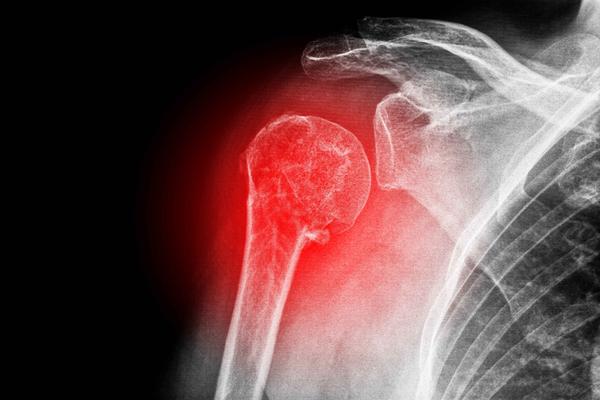

骨转移肿瘤的临床表现与诊断

骨转移瘤临床表现,昆明骨转移肿瘤医院哪家好-昆明医科肿瘤医院骨转移肿瘤是指恶性肿瘤细胞通过血液或淋巴系统侵入骨骼并在骨组织内生长的一种恶性肿瘤。其临床表现多种多样,包括骨痛、骨折、瘫痪、贫血、乏力等症状。及早发现和诊断骨转移肿瘤是治疗和预后的关键。一、临床表现...